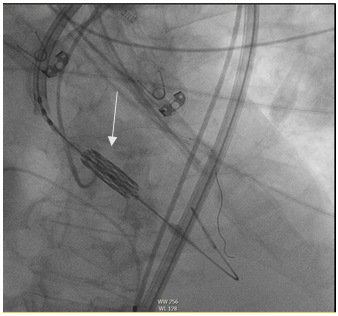

In the previous study, it appeared that the origin of the left common trunk could be compromised by the TAVI stent, so it was decided to perform left coronary protection with a 3.5 (6F) EBU catheter, Asahi Sion angioplasty guidewire and NC angioplasty balloon through the right brachial artery.

Percutaneous therapeutic access through the right femoral artery, successful implantation of Sapien 3 valve, nº26 (Edwards) (Figure 7 and 8).

Figure 7 Alignment of valve prosthesis.

Figure 8 Implantation of aortic prosthesis.